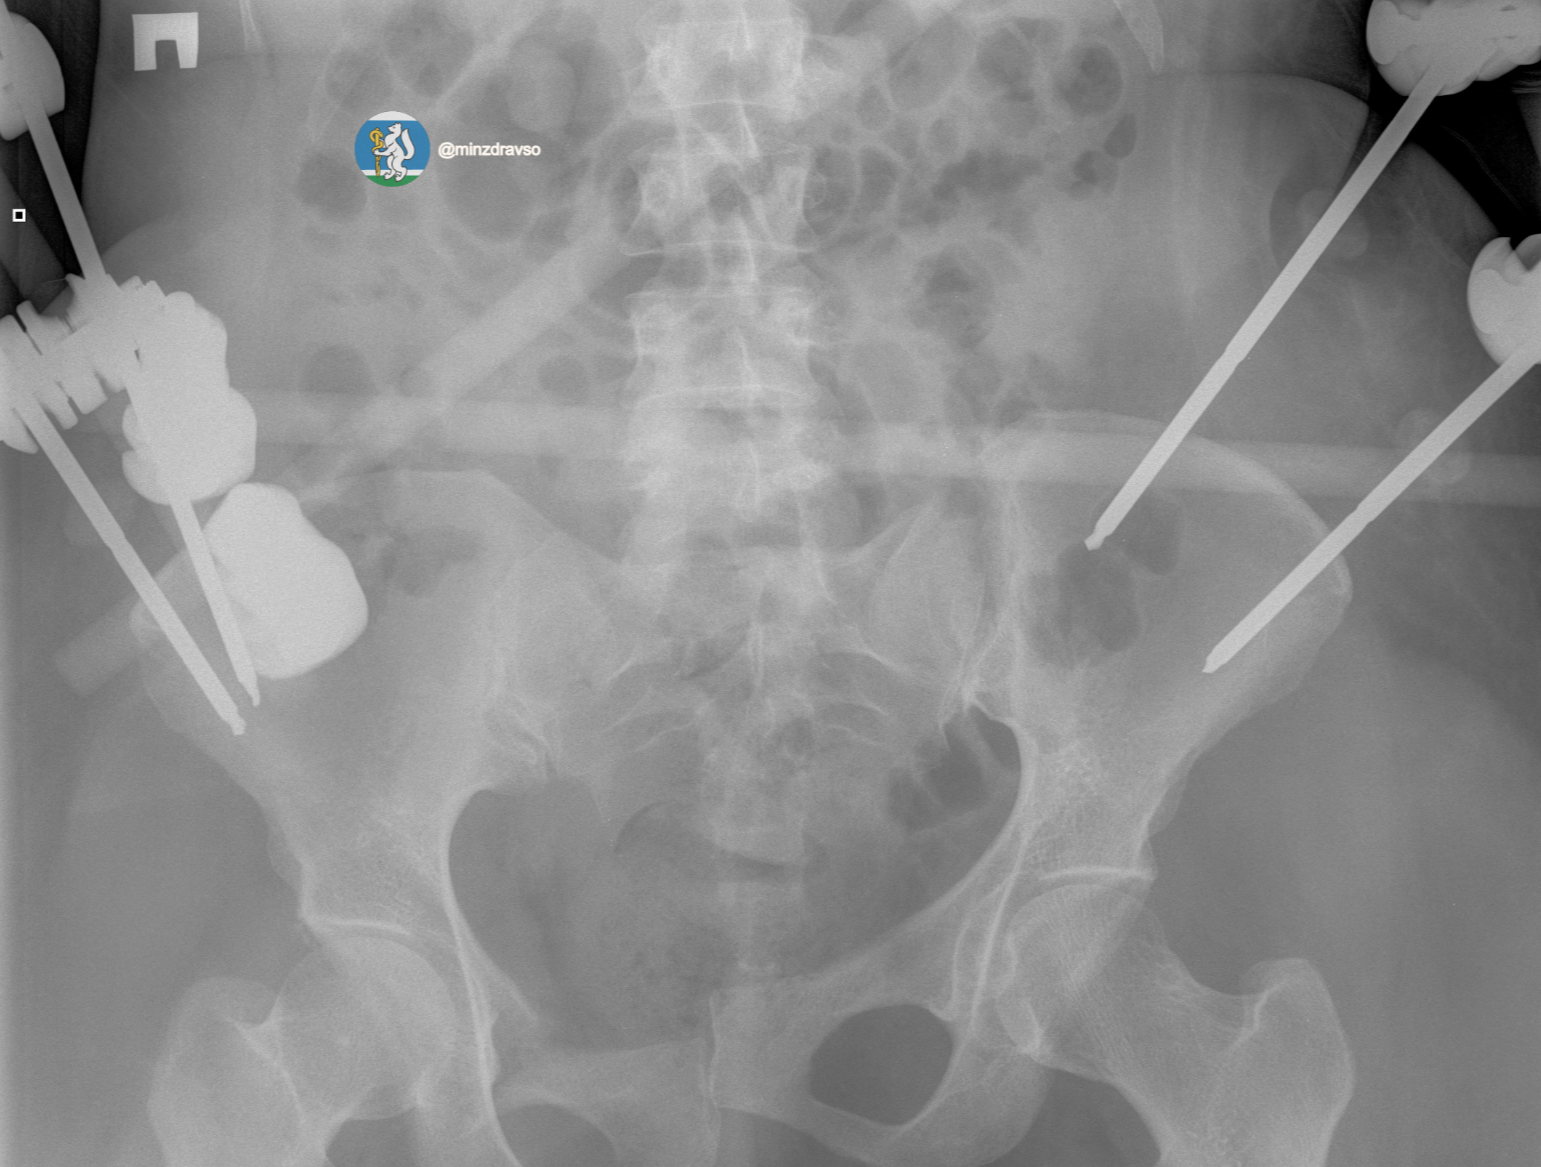

В течение первых 15 минут были проведены все необходимые исследования. Врачи диагностировали тяжелую политравму, включающую закрытую черепно-мозговую травму, ушиб головного мозга, повреждение челюстно-лицевых костей, ребер, двусторонний пневмоторакс, оскольчатый перелом правой ключицы и раздробленные кости таза. Крайне тяжелое повреждение таза представляло высокий риск массивной кровопотери, поэтому борьба за жизнь пациентки началась с немедленной стабилизации ее состояния.

«Пострадавшей оказали помощь, которая отвечает всем современным требованиям к лечению политравмы. Чтобы стабилизировать зоны переломов и купировать болевой синдром, врачи скрепили отломки костей всех поврежденных сегментов костей и таза аппаратами внешней фиксации. Большую роль сыграл мультидисциплинарный подход: спасти пациентку удалось благодаря совместной работе анестезиологов-реаниматологов, травматологов-хирургов и нейрохирургов», – рассказал заведующий травматологическим отделением Городской больницы №36 «Травматологическая», к.м.н. Евгений Козлов.